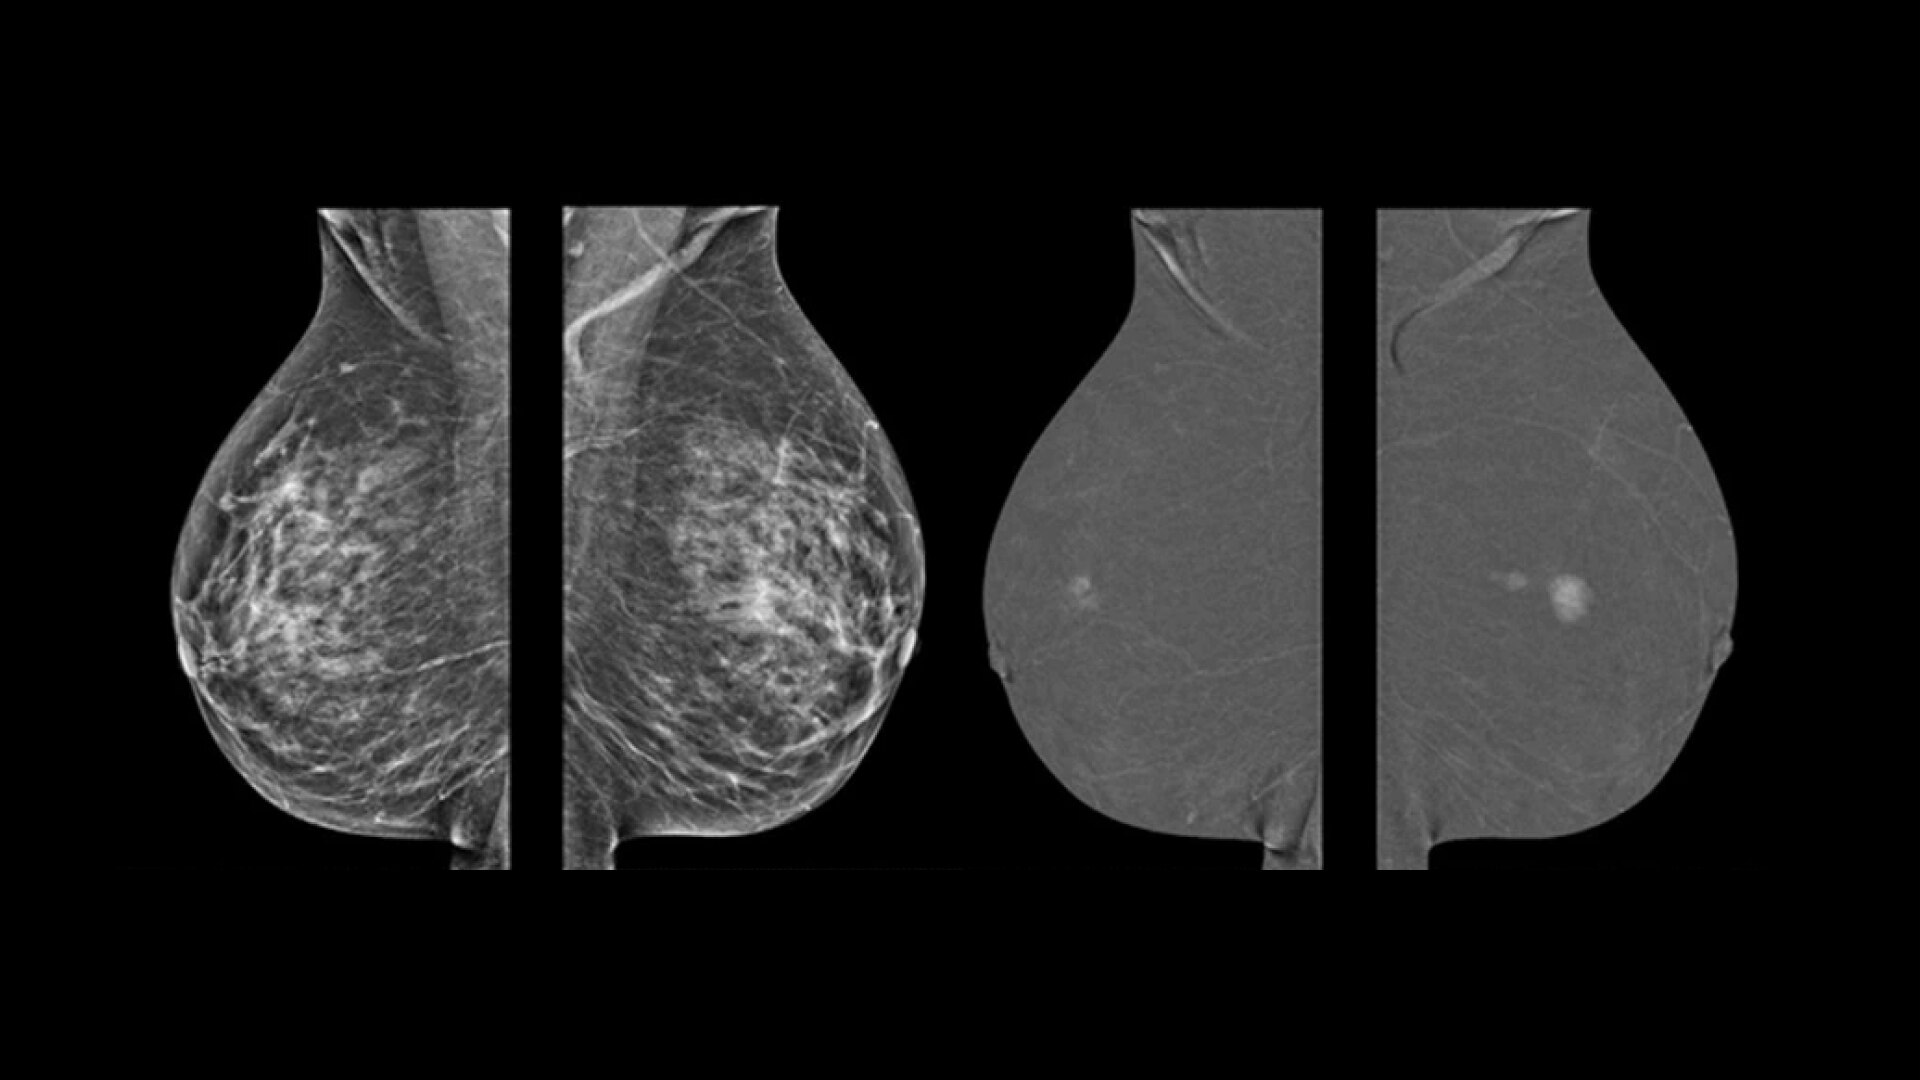

Qualidade de imagem excepcional para precisão de diagnóstico

As nossas equipes de engenharia trabalham apaixonadamente para desenvolver soluções concebidas para alcançar uma qualidade de imagem excecional:

• 2D com eConstrast HD: o novo processamento melhora o fluxo de trabalho de leitura, reduzindo a necessidade de exibir manualmente nossas imagens e a confiança do radiologista em nossa qualidade de imagem 2D.

• 3D com Asir: a reconstrução permite técnicas de gerenciamento de artefatos que reduzem muito a propagação de clipes/microcalcificações, em detrimento do tempo de computação extra (Asir é mais longo do que a reconstrução FBP.

• CEM com NIRA: graças ao novo algoritmo de recombinação, o impacto dos artefatos é significativamente reduzido para todos os leitores e pode melhorar a confiança no diagnóstico⁵.